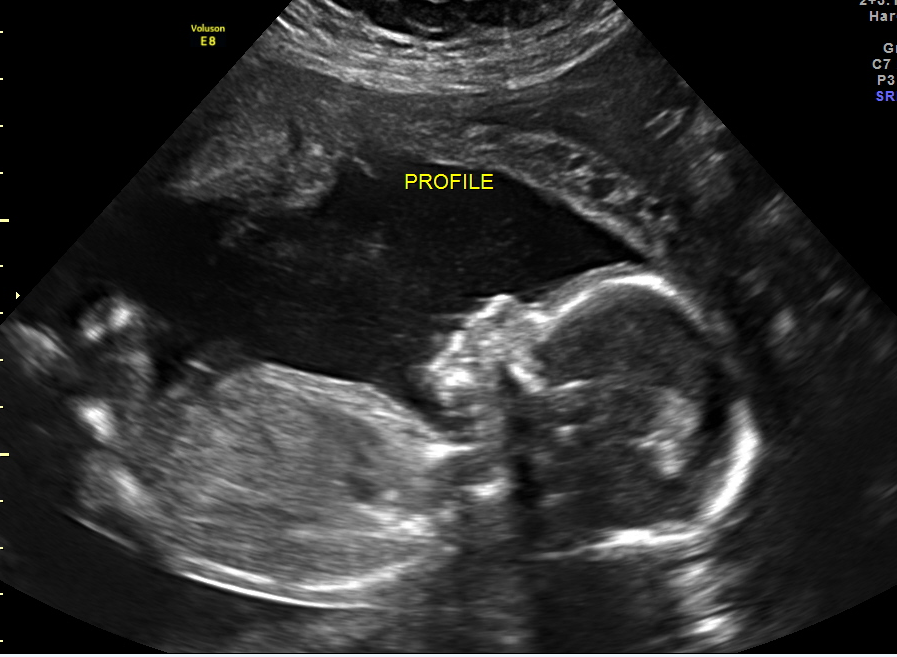

Had my anatomy scan today. She's measuring a little on the small side, 9 oz at 19w 5 d, which they said is in the 12th percentile, but otherwise she's doing great!